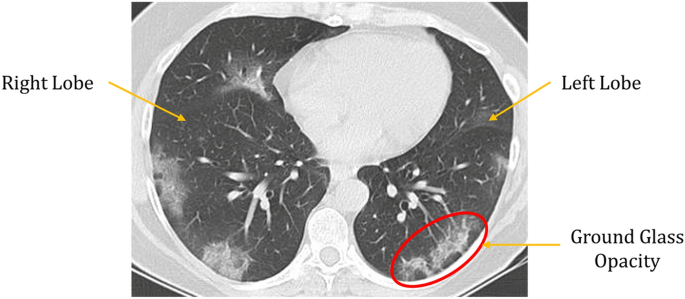

Sharda hospital, the l3 covid facility in greater noida, has reduced its chest ct scan rates from rs 5,500 to rs 2,500, said officials on monday. Implementation of appropriate precautionary safety measures, chest ct protocol optimization, and a standardized reporting system based on the pulmonary findings in this disease will enhance the clinical utility of chest ct. Unlike an mri, a ct scanner is an open machine—you are not enclosed and can see completely around yourself. This test determines the antibody response to a recent covid infection you may have had detects past infection (not active covid infection) book now. But imaging does have a limited role to play: Covid antibody igg @ rs.

When used with lab tests, a medical history and. Implementation of appropriate precautionary safety measures, chest ct protocol optimization, and a standardized reporting system based on the pulmonary findings in this disease will enhance the clinical utility of chest ct. However, up to 50% of patients may have a normal chest ct within the first two days after the. Know whether you have met this invisible enemy already or not yet. The mean time for chest ct reporting was 11.2 ± 3.6 min.